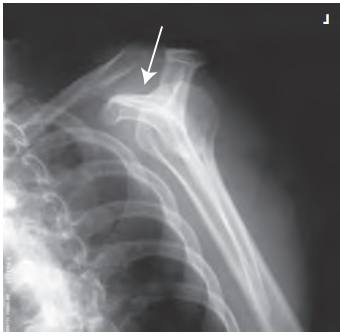

영상평가

- arcromion(견봉)의 전체적인 모습이 잘 보여야 한다.

- scauplar(견갑골)은 Y자 모양이 나와야 한다.

- supraspinauts(극상근)이 차지하는 공간이 잘 나와야 한다.

- AC joint(견쇄관절), scapular가 잘 보여야 한다.